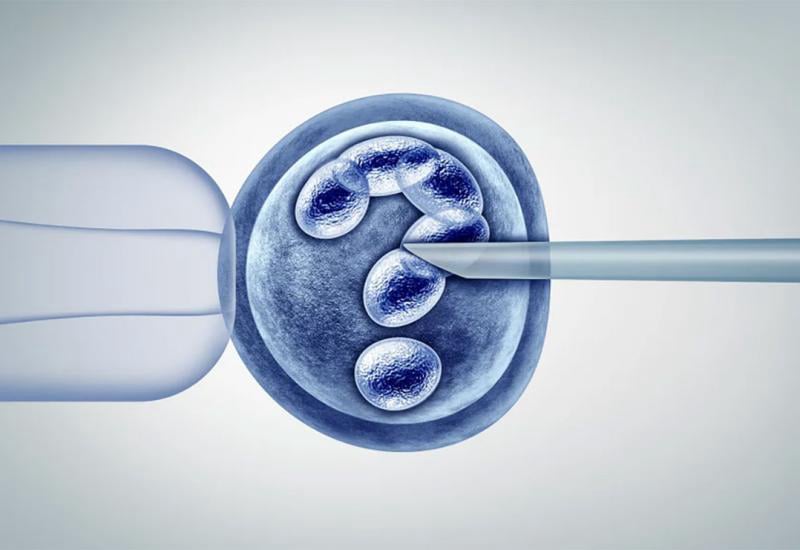

BMPO u FBiH - Presjek stanja

IVF ostaje uglavnom igra brojeva...

Zašto je u FBiH napravljeno zantno manje IVF ciklusa u odnosu na Europski prosjek?